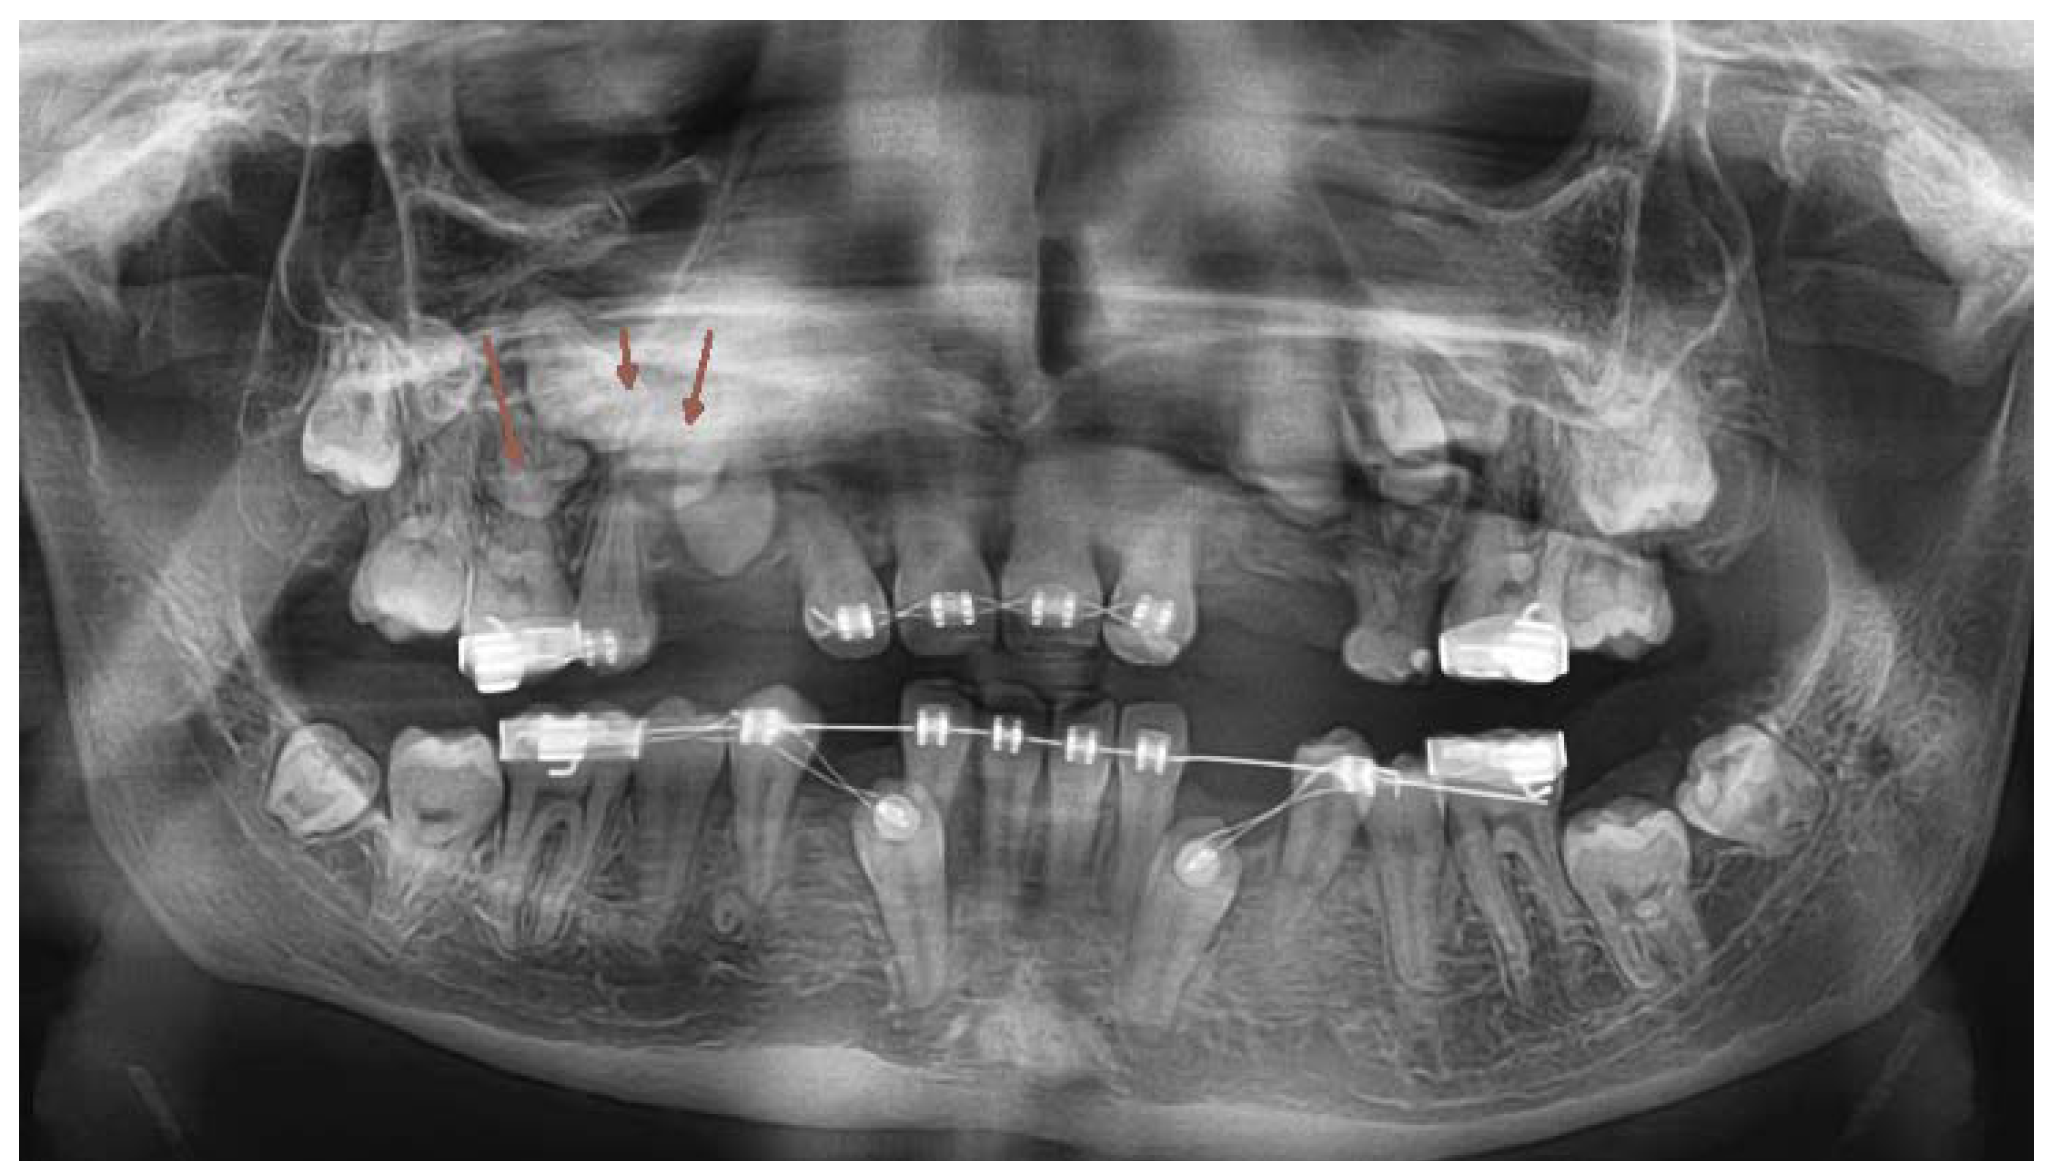

In April 2018, the patient´s age was 13 years 5 months, the dental age was 8 years. Under general anesthesia, two supernumerary teeth in the lower right and one in the lower left quadrant were extracted. (Figure 5.,10.) 3 primary teeth were extracted as well (73,83 and 84). This cleared the way for the anticipated spontaneous eruption of lower canines and first premolars. (Figure 10.) One supernumerary tooth with an underdeveloped root in the area of 35 was subsequently extracted from the chair under local anesthesia. (Figure 10.) Unfortunately the path of eruption of the 33 and 43 was too close to the apical area of the 42 and 32, (Figure 10, 11.), so an additional surgical intervention was planned, in local anesthesia, to expose the lower canines and redirect their eruption. This required already a fixed orthodontic appliance placement to anchor proposed lower canine traction.

Figure 10. OPG x-ray after the 2nd surgical intervention under general anesthesia. (2018).

Fixed Appliance Orthodontic Treatment- Phase 2

A new OPG x-ray was taken in November 2022 (Figure 17). The upper incisors were in place and their roots were fully matured. The 45 was already in the correct position, the 35 was in a slightly crowded position, but the lower canines cooperate well with the orthodontic forces. But at this time was already clear, that newly formed supernumerary teeth started to mineralize their crowns in the upper alveolus, two in the upper right and one in the upper left quadrant. (Figure 17). It was necessary to plan a third surgical intervention under general anesthesia.